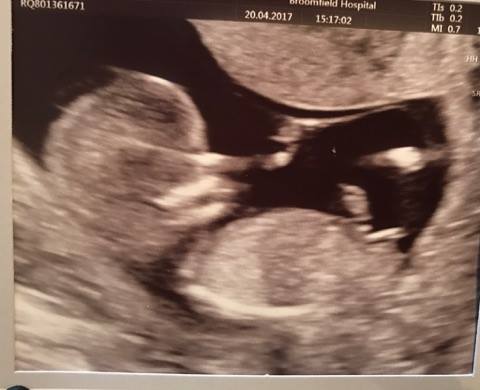

12+3 clear nub pic.. guesses pleease?? will update when i find out!